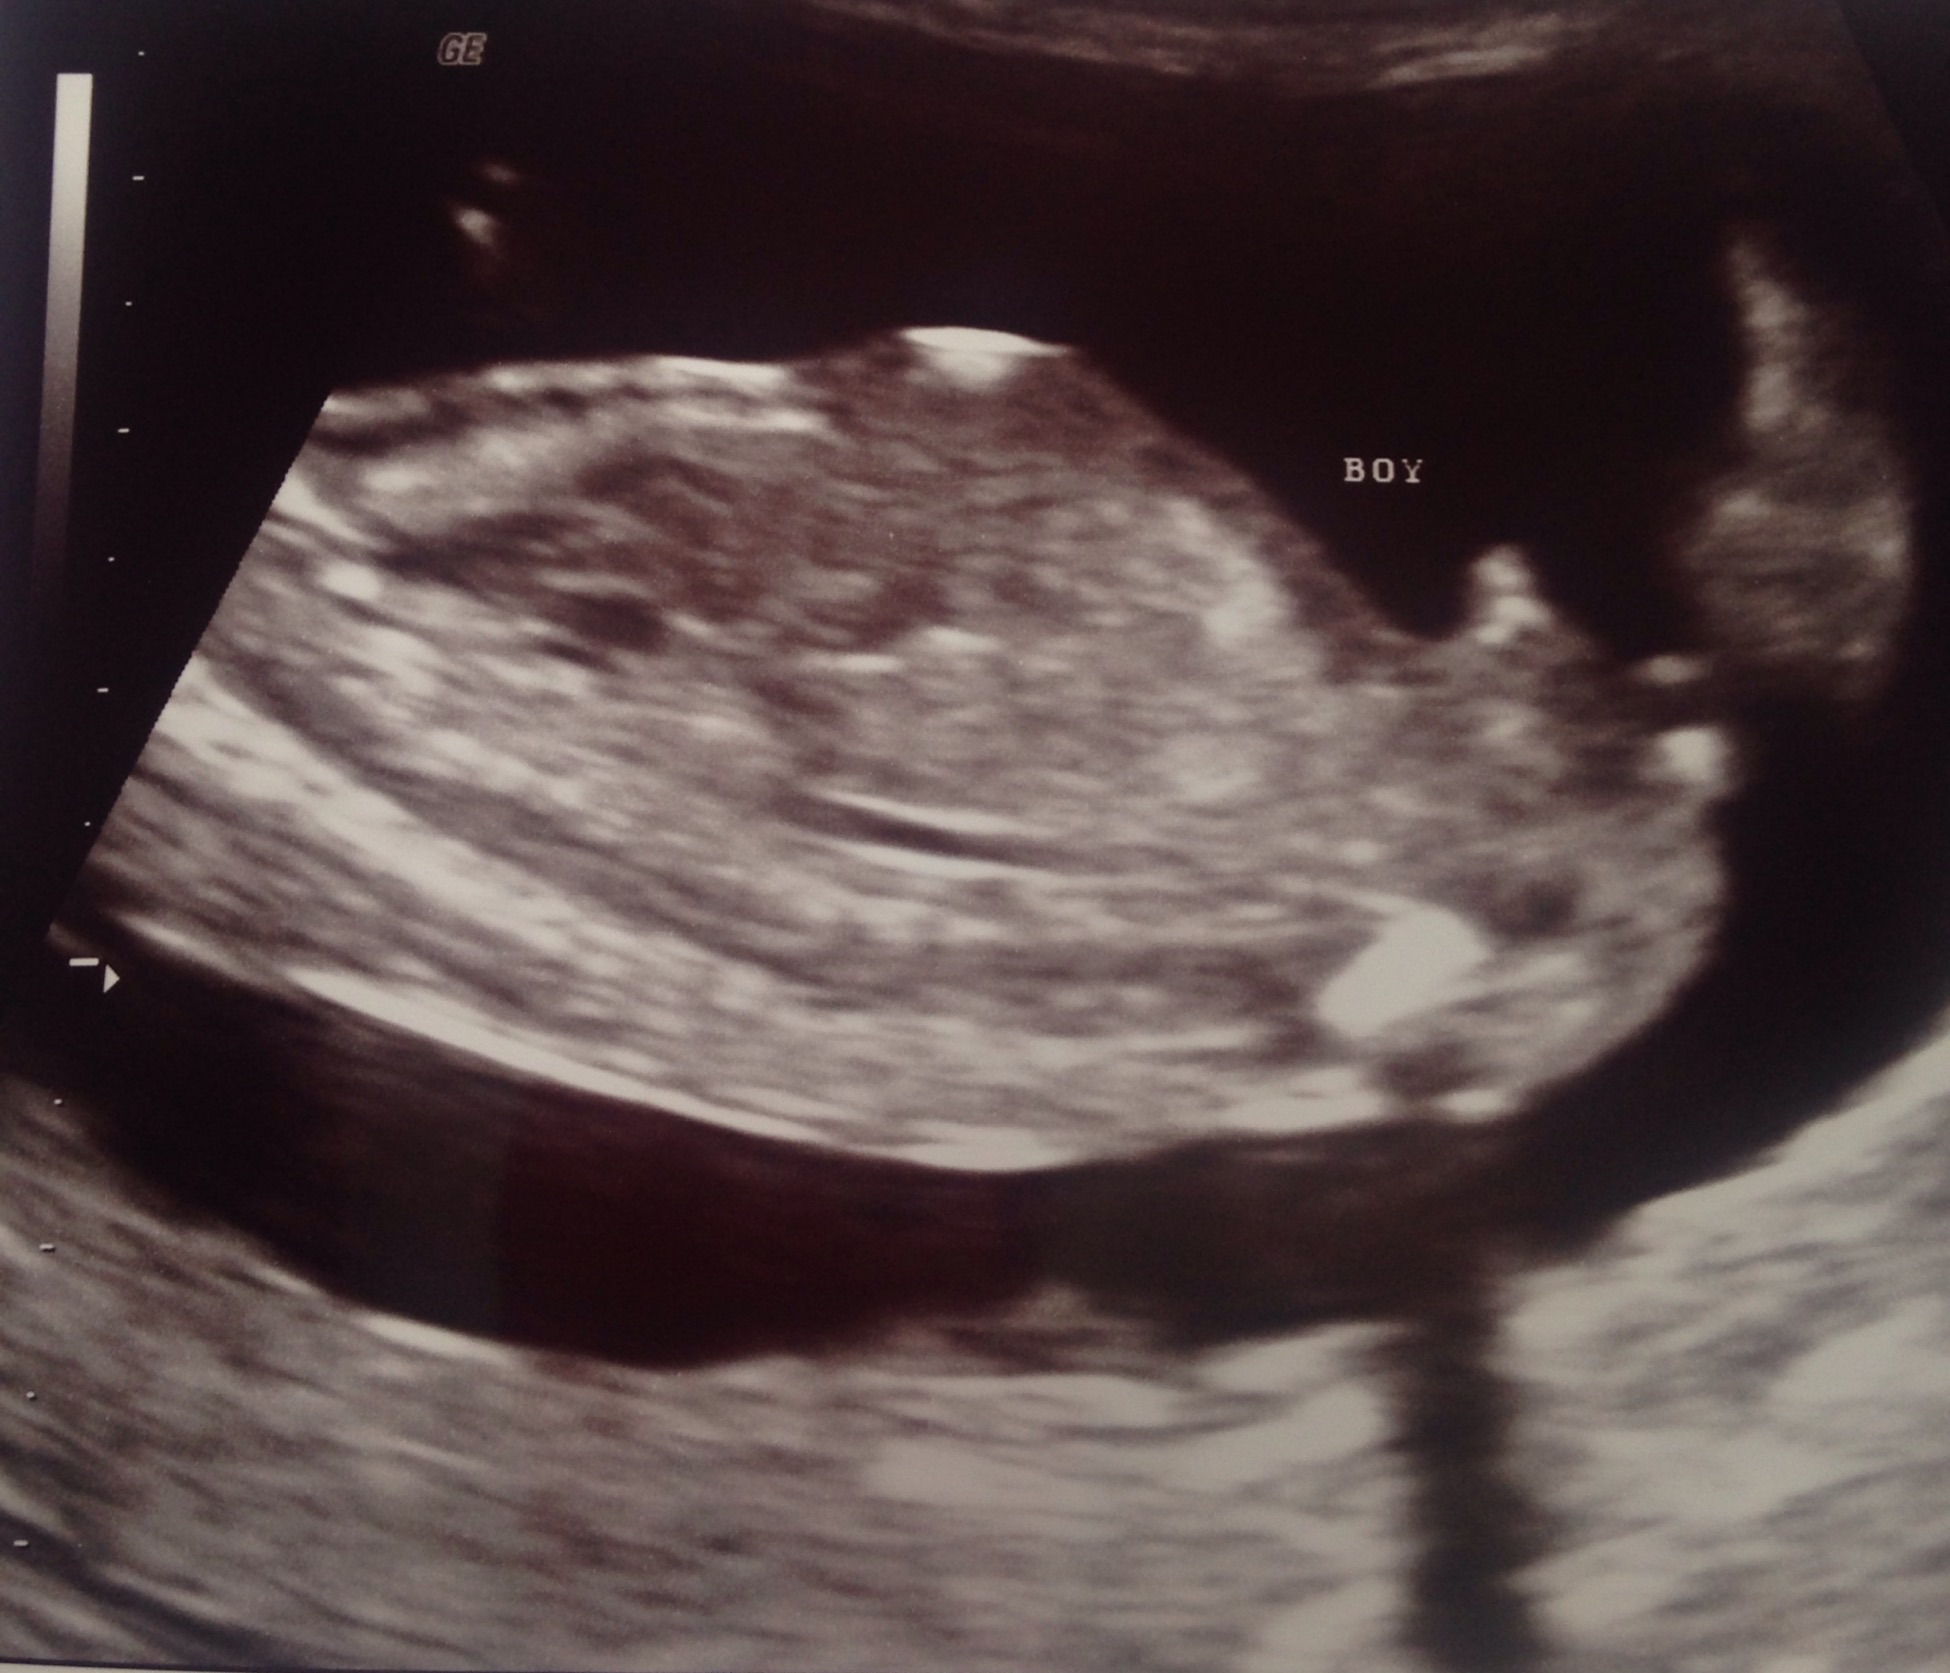

Confirmed boy but slight doubt!?

Hi all 😊 I had a gender scan at 15 + 3 and was told boy. The only reason I'm slightly doubtful is first she said 'hang in its got the cord between its legs' wiggled the devise and said 'yep it's a boy' Just a tad concerned that it is the cord. I don't want to start buying things until I get a second opinion at my 20 weeks scan but thought I'd post the pics to see what you all thought. Also I can't tell whether the potty shot is between the legs or side on 😕 Thank you 😊 xxx

Attachment 26075